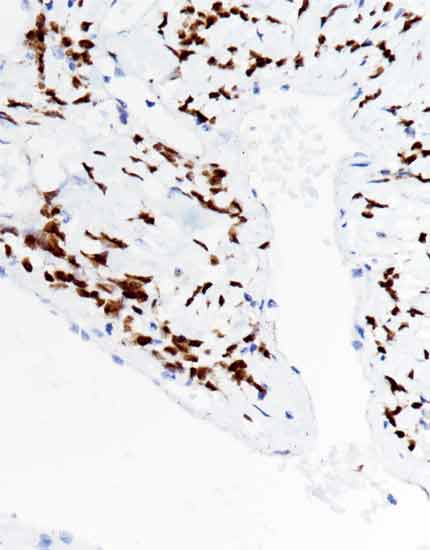

产品名称:Topo II α

产品编号:MAB-1099

阳性部位:细胞核

图片描述:

乳腺癌,Topo II α染色,细胞核阳性